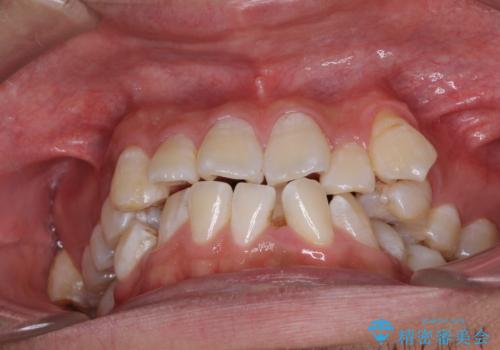

- 前歯の叢生と八重歯を気にして来院された患者様です。

叢生が強く、奥歯の咬合も左右差が大きかったため、上下左右4本を抜歯して、ワイヤー矯正を行うこととしました。